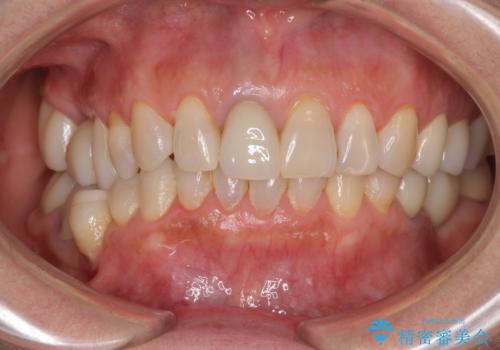

金属を全てセラミックに メタルフリー治療

- 口腔内にある銀歯を全て外したいとのことで来院された患者様です。

土台に含まれている金属も含め、口腔内の金属は全て除去し、抜歯しなければならない歯は抜歯し、オールセラミッククラウンやセラミックインレーにて治療することとしました。

口の中を一切気にしなくて良くなり、患者様には大変満足していただきました。